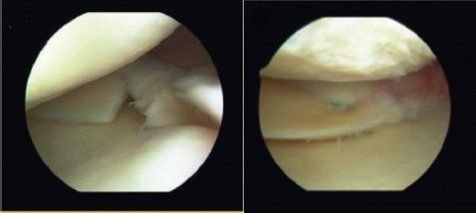

If you have a knee problem, in most situations I believe it will be helpful for you to have such an MRI scan of your knee - to make or support a diagnosis or to exclude other reasons for your problem. MRI scans are particularly useful in the evaluation of meniscus tears, and tears of the anterior cruciate ligament (ACL) and other ligaments. If your main problem is knee pain I believe you should in most circumstances as part of the investigation have an MRI scan of the knee, and indeed I feel you should not have an arthroscopy unless you have had an MRI evaluation. The price has declined considerably over recent years, making MRI a much more affordable aid to diagnosis, and today a knee MRI is close to 400 euros in Denmark (where I practice).